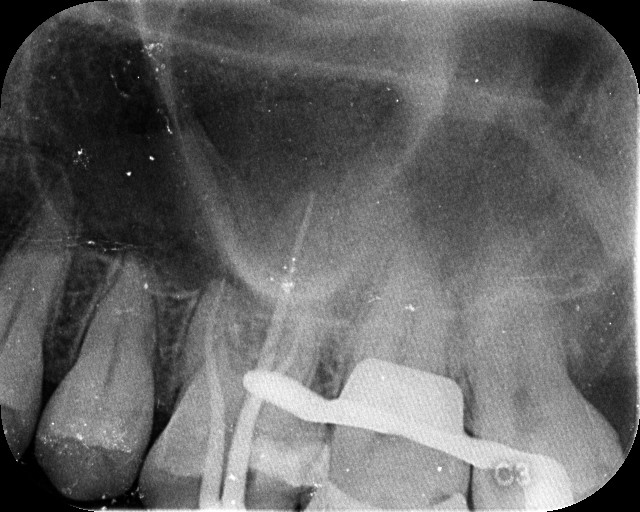

At Microsmiles, every root canal is performed under a high-resolution dental microscope, allowing our specialists to treat even the most complex canals with pinpoint accuracy. This level of detail isn’t just high-tech-it leads to faster treatment, fewer appointments, and long-lasting results.